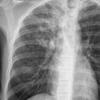

TB - active

active TB